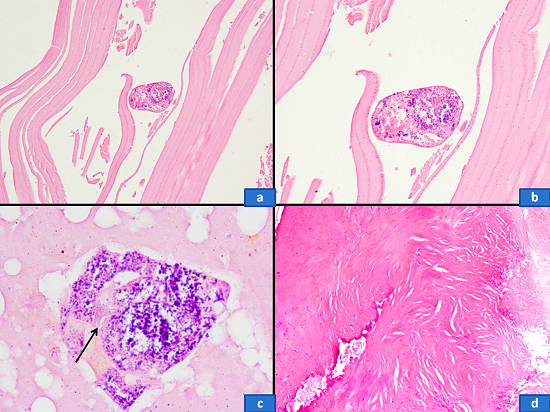

Since most of the imaging findings were consistent with an ovarian neoplasm, an exploratory laparotomy was performed. A cystic mass (8 × 8 cm) of pelvic origin was found buried under the loops of intestine and adherent to the sigmoid colon postero-laterally and to the bladder wall anteriorly. By sharp dissection, the bladder and gut walls were separated from the cyst wall. During the surgical procedure, an accidental injury broke up the cyst wall allowing the drainage of some cystic fluid, revealing many scolices and yielding the macroscopic diagnosis of hydatid cyst. After sealing the puncture site with hemostatic clamps, the whole mass was carefully enucleated (Figure 2A). Underneath the sigmoid colon, another small palpable lump was dissected and it appeared to be the right ovary with cystic changes. Although left ovary appeared normal it was also removed. Thorough peritoneal lavage was performed with saline followed by external abdominal drainage. The surgical specimen showed gross features of an echinococcal cyst (Figure 2B), and microscopic examination revealed the ectocyst, the pericyst, and the hydatid scolices (Figure 3). Her postoperative period was uneventful and she was prescribed albendazole (400 mg) tablets twice daily for 1 month. At regular follow-up for 6 months, no further recurrence was found clinically or on imaging.

An echinococcus cyst consists of an outer acellular laminated membrane white in color (like a hard-boiled egg), which is called an ectocyst, and an inner germinal layer called an endocyst. The germinal layer is cellular, consists of nuclei embedded in a protoplasmic mass, produces brood capsules with scolices, and secretes hydatid fluid and forms the outer layer. When ruptured, the draining fluid can give rise to an anaphylactic shock due to high antigenicity. Hosts tissue reaction produces a thick fibrous layer outside the ectocyst, which is known as a pericyst.